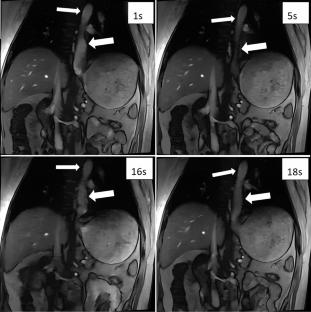

In the prospective study, 40 healthy volunteers and 30 GERD patients underwent real-time cine MRI using an undersampled low-angle gradient echo sequence (50 ms/frame) with deep-learning reconstruction, to monitor the gastroesophageal junction (GEJ) and observe the reflux of the contrast agent during the Valsalva maneuver. The width of the lower esophagus, the length of the lower esophageal sphincter (LES), the end-expiratory and post Valsalva maneuver His angle were measured.

There were no statistical differences between the two group either in lower esophageal width (14.06 ± 1.50 mm vs. 14.75 ± 1.57 mm, P > 0.05) or LES length (25.20 ± 1.46 mm vs. 24.39 ± 1.68 mm, P > 0.05). The end-expiratory His angle (84.45 ± 18.67°) and post Valsalva maneuver His angle (101.53 ± 19.22°), and the differences between them (17.08 ± 5.65°) in the GERD group were greater than those in the healthy volunteers (71.51 ± 18.01°, 86.09 ± 18.24°, 14.57 ± 3.88° respectively, P < 0.05). Reflux was induced in 8 cases of GERD group including 4 cases with hiatus hernia and not observed in healthy volunteers. The AUC for diagnosing GERD were 0.702, 0.737 and 0.634 for end-expiratory, post Valsalva maneuver His angle and their differences, when combined with real-time MRI was 0.823, with a sensitivity of 86.67% and a specificity of 67.50%.

Real-time MRI can display dynamic swallowing and reflux at the GEJ. The His angle can serve as a morphological indicator for diagnosing GERD with MRI.